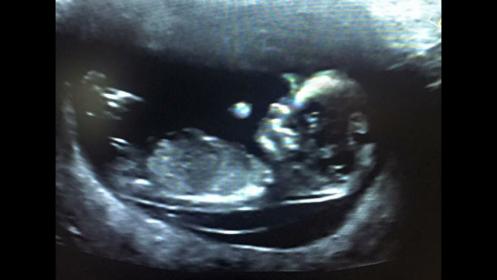

Attachment 28340Asking for my cousin, what are your thoughts on this nub please??

12+3 I believe....

I think it's rising too so boy :)